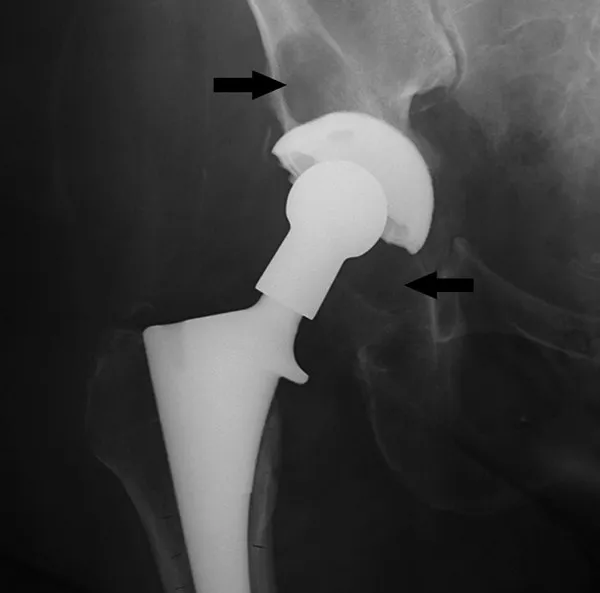

- Radiology: Radiolucent lines >2mm at interface, component migration/subsidence.

Aseptic Loosening - Silent Sabotage

- Most common cause of late Total Joint Arthroplasty (TJA) failure; non-infectious.

- Pathogenesis: Wear particles → macrophage activation → cytokine release (TNF-α, IL-1, RANKL) → osteoclastogenesis → periprosthetic osteolysis → implant loosening.

- Clinical: Insidious onset pain, instability, ↓Range of Motion (ROM).